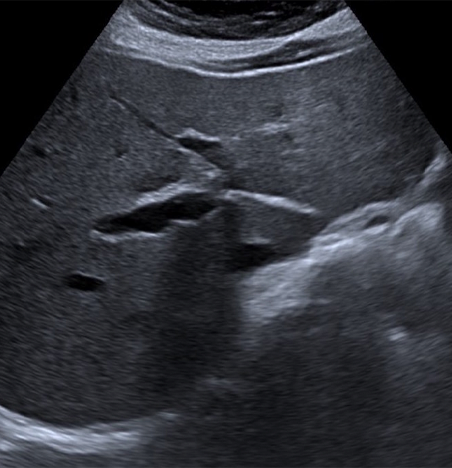

Il s’agit d’un outil performant pour l’étude :

– abdominale,

– pelvienne,

– gynécologique,

– des voies urinaires

L’échographie est précieuse en imagerie pédiatrique compte tenu de son caractère inoffensif.

Elle permet par exemple le dépistage à 1 mois de la luxation congénitale de hanche, les échographies médullaires, transfontanellaires (ETF) ou abdominales (sténose du pylore, invagination intestinale aiguë, suspicion d’appendicite…).